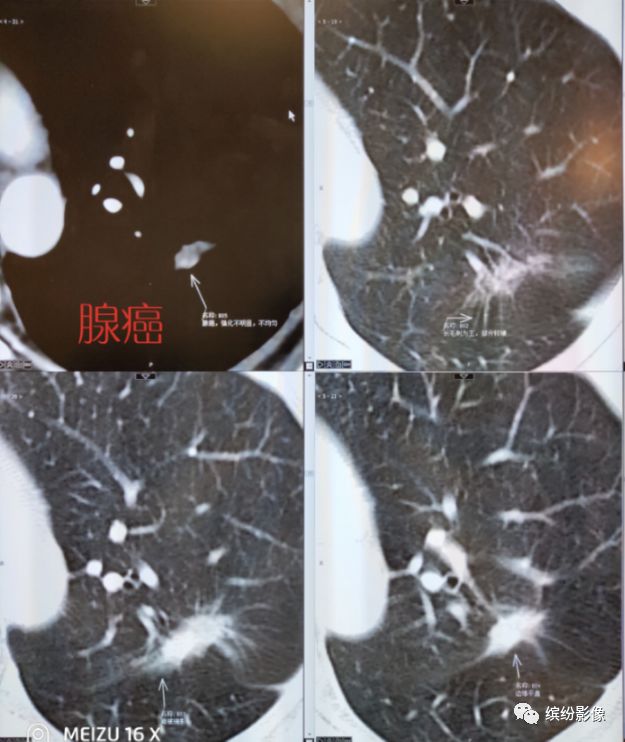

肺癌的变化有时特别快,如下例腺癌,结节明显变大增多

腺癌边缘多有GGO,毛刺较硬

低分化腺癌,有时反而分叶毛刺GGO较少

一般来说,典型腺癌是长这样的